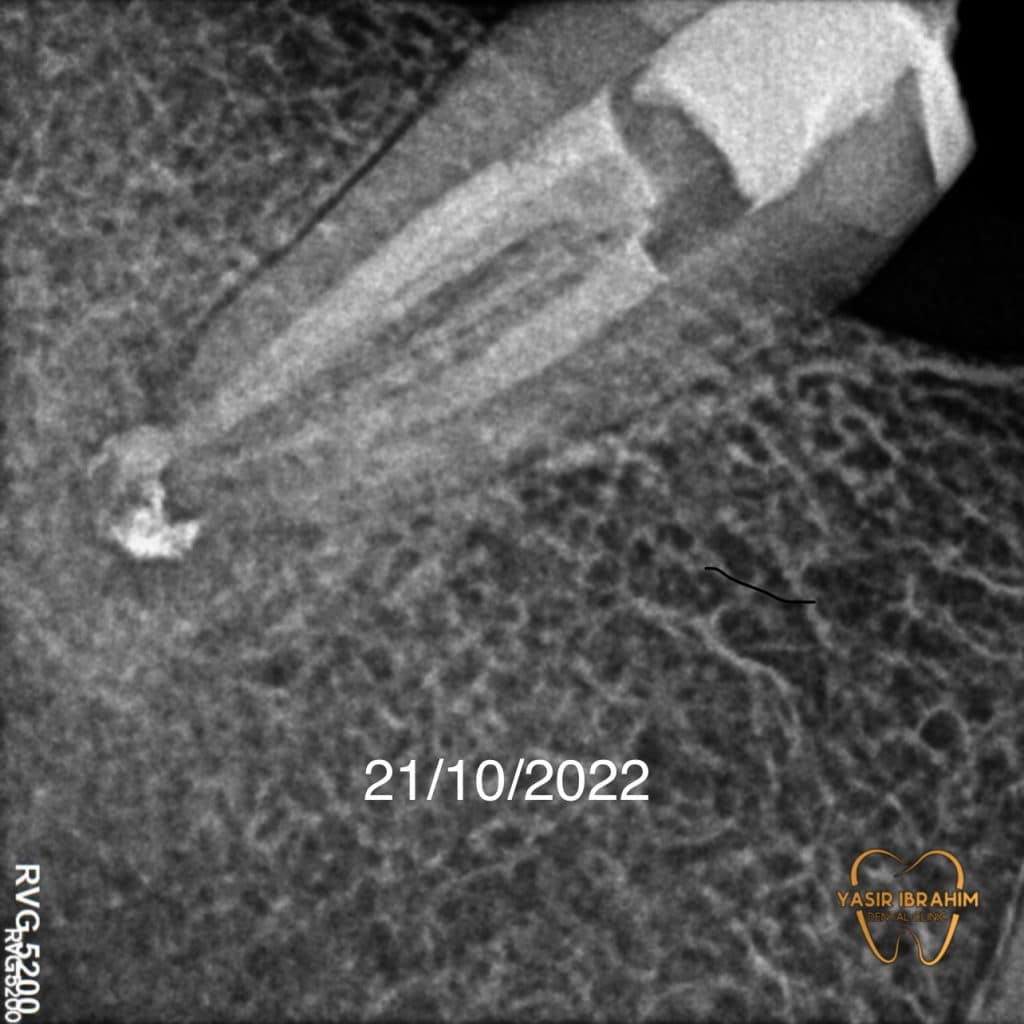

Radiographic analysis show periapical lesion With poor RCT .

Diagnosis : periapical abscess .

we notice healing of the periapical lesion by 75% With

disappearance of all symptoms, after one month of obturation by MTA.